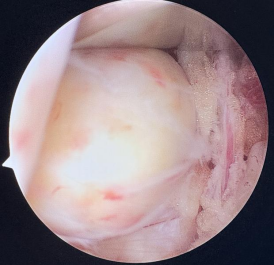

作为目前骨科领域领先的脊柱微创技术,UBE技术通过建立两个直径仅0.5—0.7cm的微小通道,将内镜、操作器械分别置入。医生可通过高清内镜画面,清晰观察脊柱内部的病变组织——无论是突出的椎间盘、狭窄的椎管,还是增生的骨赘,都能在放大视野下一目了然。相较于传统开放手术,UBE技术实现了“小切口解决大问题”:术中出血极少,创伤面积不足传统手术的1/5,术后疼痛轻,患者可快速下床活动,住院时间缩短至3—5天,极大降低了术后感染、粘连等并发症风险,尤其适用于腰椎间盘突出症、腰椎管狭窄症等常见及复杂脊柱疾病,让脊柱治疗告别“大动干戈”,迈入微创精准诊疗时代。

2.术中操作更精准:在UBE高清内镜视野下,结合3D打印模型的术前预判,医生可精准切除病变组织、植入定制化内固定物,减少对正常脊柱结构的损伤;